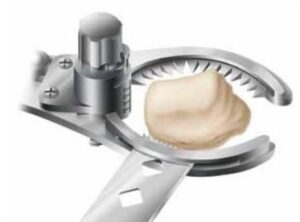

Η οπίσθια επιφάνεια της επιγονατίδας και η πρόσθια του μηρού αντικαθίστανται ανάλογα του μεγέθους και της ανατομίας του γόνατός σας με το κατάλληλο εμφύτευμα. (εικόνα 9 ) Ειδικά όσον αφορά τις οστεοτομίες στην πρόσθια επιφάνεια του μηρού, η τεχνική και οι χρησιμοποιούμενοι οδηγοί έχουν επίσης εξελιχθεί σοβαρά. (εικόνα 10 εικόνα 11 και εικόνα 12)